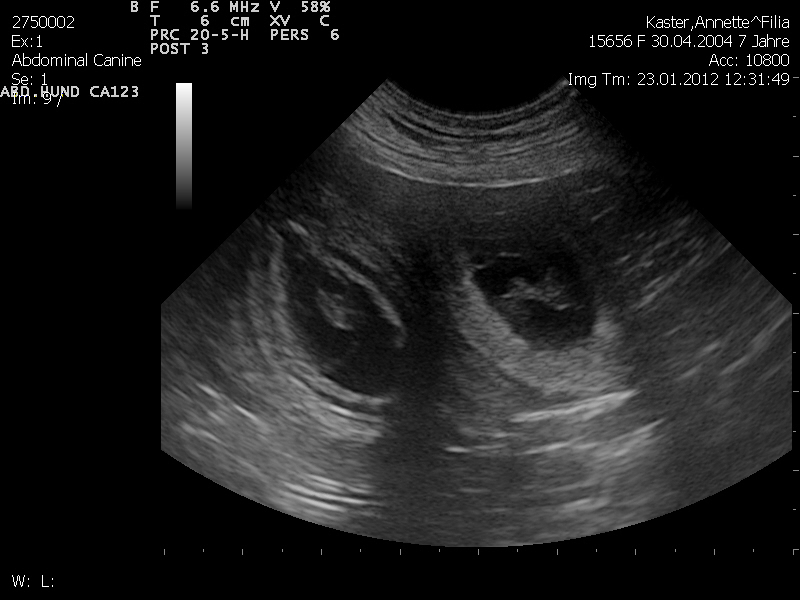

Filha wird etwas vorsichtiger. Läuft noch wie gehabt, kann fressen ohne Ende. Ein kleines Bäuchlein ist schon zu sehen!23.01.2012

(25. Trächtigkeitstag)Filha ist trächtig!!!!

5. Progesterontest: 20,5 ng/ml (Alles im grünen Bereich!)22.01.2012